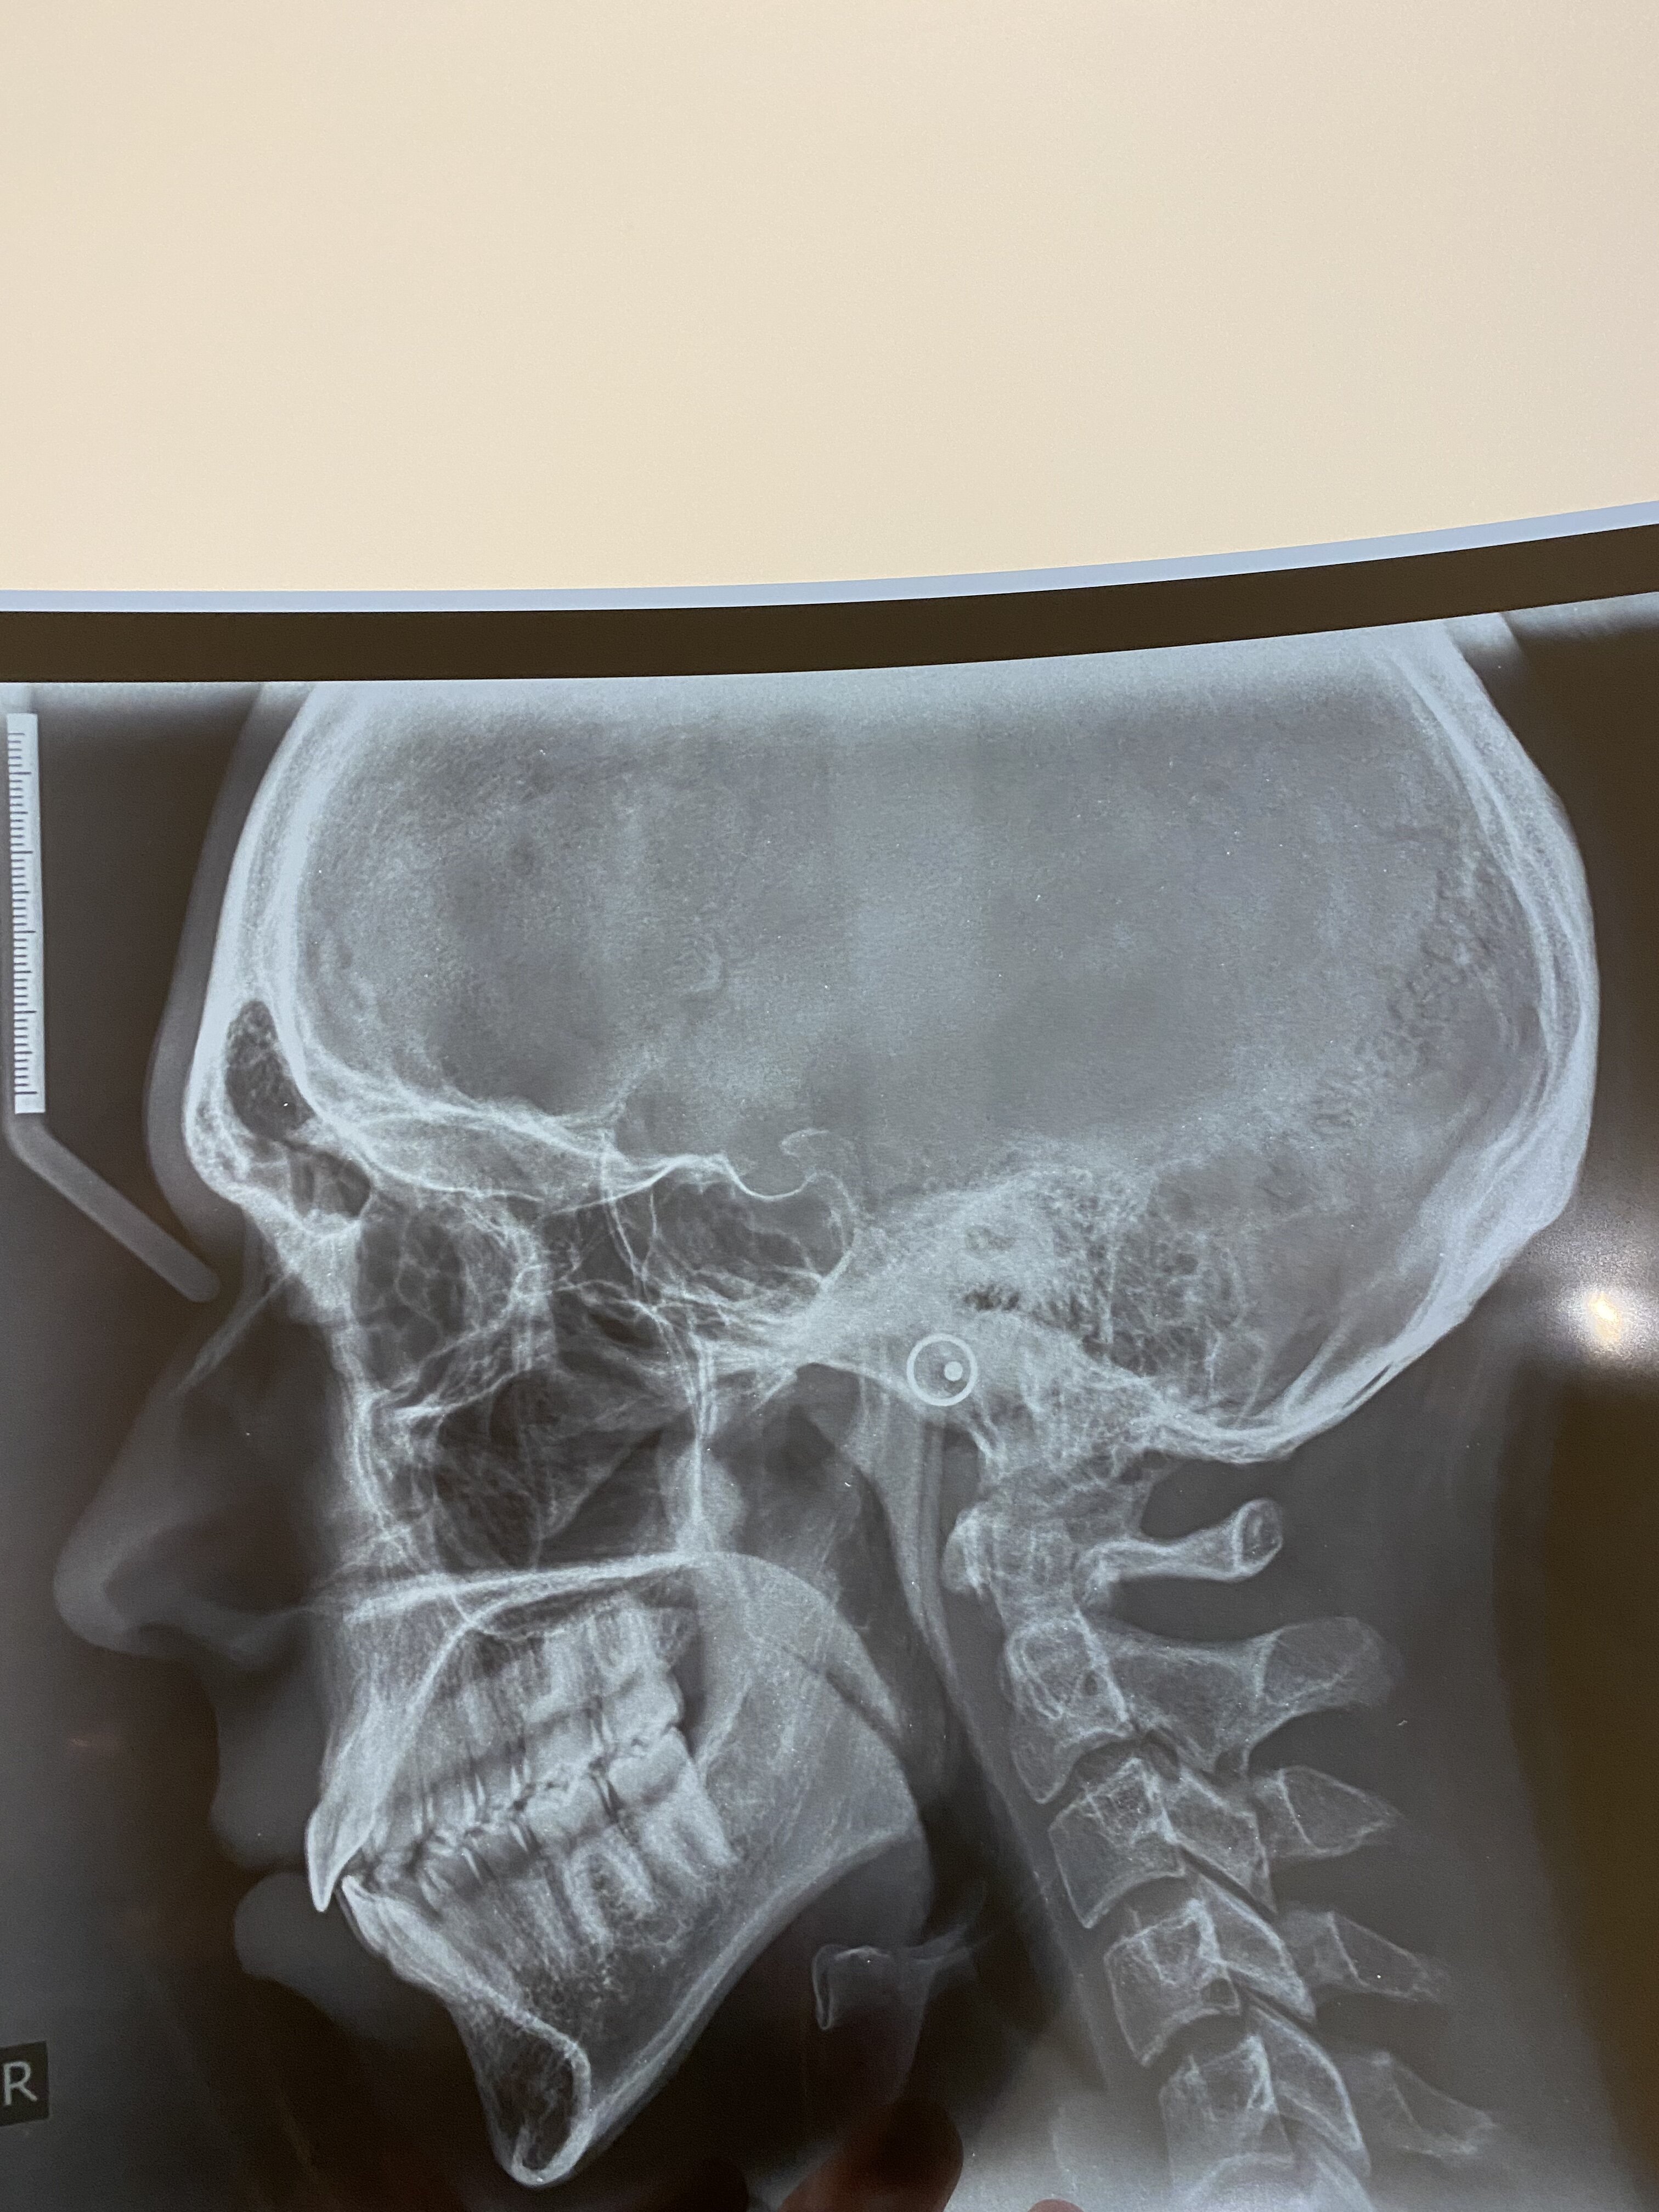

DJS + Genioplasty pre-planning

Mandible and maxilla, osteo ues or osteectomies of, involving 2 such procedures of each jaw; including transposition of nerves and vessels and bone grafts taken from the same site and stabilisation with fixation by wires, screws, plates or pins or any combination.